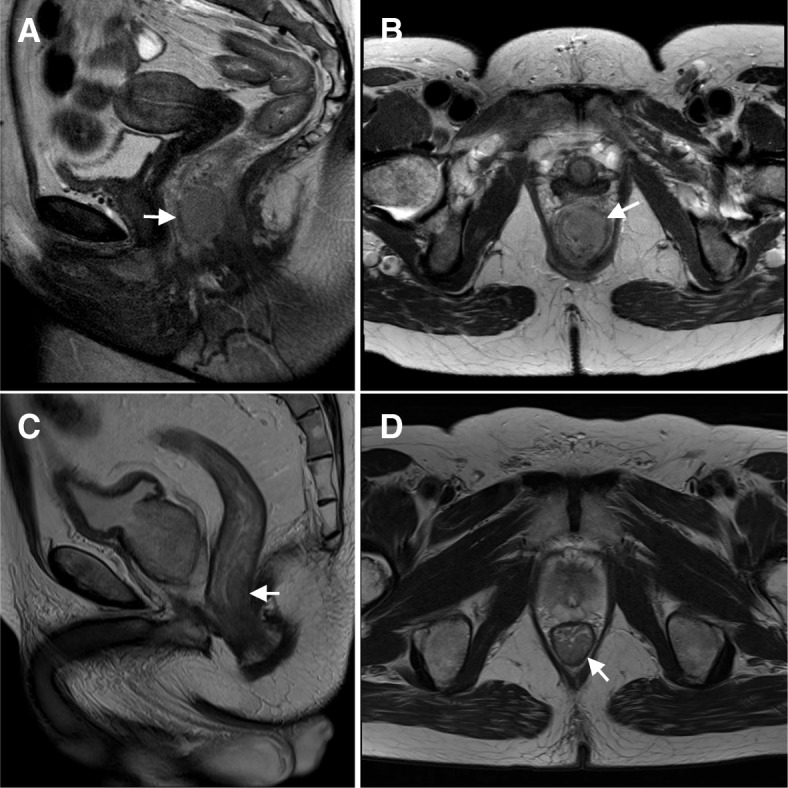

Fig. 2.

T2-weighted MRI of the pelvis of the female case shows a 3-cm lesion in the anal canal extending into the anorectal junction (a. sagittal, b. axial). MRI of the male case also demonstrates a T2 lesion measuring about 3 cm beginning at 2 cm from the anal verge (c. sagittal, d. axial)

A 60-year-old woman sought medical attention after a 2-month history of minor rectal bleeding and an anal nodule. On physical examination, a 3-cm mobile anterior ulcerative mass in the anal canal was palpable, beginning at 1 cm from the anal verge with no extension to the anorectal junction. No nodes were appreciated in the inguinal regions. A biopsy revealed an invasive squamous cell carcinoma, well-differentiated (Fig. 1a). Staging computerized tomography (CT) of the thorax/abdomen/pelvis did not show any lymphadenopathy or distant metastatic disease. Pelvic magnetic resonance imaging (MRI) demonstrated a 3-cm mass in the anal canal extending to the anorectal junction (Fig. 2a and b). There was no pelvic or inguinal lymphadenopathy. Her laboratory investigations including HIV-1 and HIV-2 serology were negative. A recent Papanicolau smear of the cervix was reported to be negative for intraepithelial lesion or malignancy.

While the female was undergoing chemoradiation, her husband, with whom she has been married for over 30 years, requested a screening colonoscopy during his regular urological follow-up. The investigation revealed an anal mass that was biopsied and demonstrated a poorly-differentiated squamous cell carcinoma with prominent lymphoid infiltration (Fig. 1b). This 63 year-old man was largely asymptomatic. After diagnosis, he was referred to the same cancer centre where his wife received oncological care. On physical examination, an ulcerative exophytic mass was seen, measuring approximately 3 cm in maximum dimension, located over the posterior third of the anal canal at 2 cm from the verge. The mass extended to the anorectal junction. No inguinal nodes were clinically suspicious. Staging CT and MRI revealed at least four suspicious mesorectal nodes and a 1.8-cm left external iliac lymph node. There was no evidence of distant metastatic disease. On MRI, the maximum tumor dimension of the primary was 3 cm (Fig. 2c and d). Similar to his wife, this man’s HIV serology was negative. He was a non-smoker. There was no previous history of sexually transmissible disease, and he denied any receptive anal intercourse or sex with men. He was on tamsulosin 0.4 mg and dutasteride 0.5 mg for benign prostatic hyperplasia.